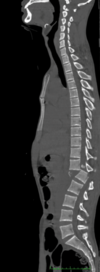

T11 compression fracture (wedge-shaped) New/acute injury (paraspinal edema present)

48

What is the diagnosis? What finding on the AP view confirms this?

L2 burst fracture Widening of interpedicle distance | indicates posterior element fracture

49

Is this injury stable or unstable? What is the appropriate follow-up?

Unstable Emergency transport | 2-3 columns of Denis involved